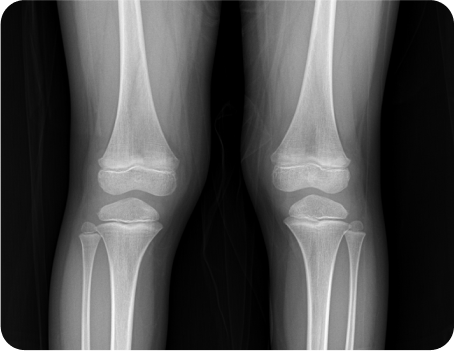

자세 부정렬을 동반한 성장부진

몸은 체형이 휘거나 구부정한 경우 성장판에 자극을 충분히 받지 못하거나 관절에 무리한 자극이 가게 되어 뼈의 성장 불균형 또는 장애를 초래하게 됩니다.

성장판 활성도 및 호르몬 검사 등의 기능적인 검사부터 체형과 측만증, 휜 다리 등의 구조적인 검사까지 놓치지 않으니까

체형교정

안짱걸음 및 측만증, 거북목, 휜 다리, 평발을 교정해 숨은 키를 찾아내고 성장의 가속도를 더함

성장추나

척추와 골반 무릎을 늘려주어 성장판 활성화,

틀어진 골반과 척추를 교정해 근육 긴장을 이완

체형이 구부정하고 틀어져 있을 경우 중력의 영향을 많이 받게 되고 틀어진 자세를 유지하기 위해 성장판 근처의 골반 근육, 종아리 근육 등의 긴장이 커지는데요.

성장판에서 세포분열을 열심히 하더라도 이런 긴장으로 인하여 성장 속도가 떨어지게 됩니다.

굽은 등과 앞으로 무너진 골반, 척추측만증이나 평발을 교정하게 되면,

숨은 키를 찾을 수 있을 뿐만 아니라 나쁜 자세와 근육의 긴장을 유지하는데 필요한 에너지가 줄어들기 때문에,

피로가 호전되고 집중력이 좋아지며 근 긴장이 해소되어 성장의 방해요인이 제거되는 효과가 있습니다.